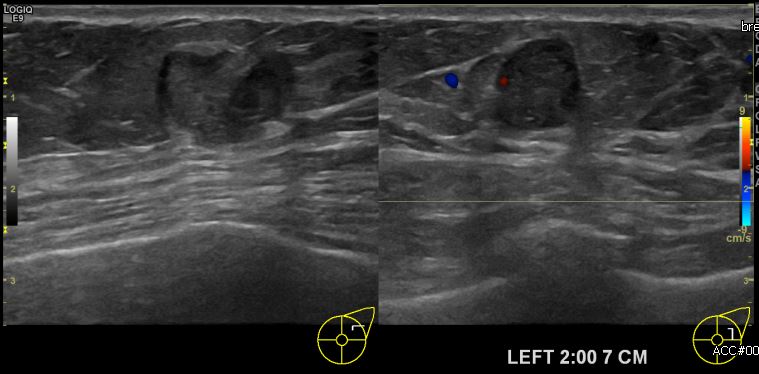

상기환자 건강검진상 이상 소견으로 내원하신 40대 여성분으로  좌측유방 2시 방향에

7cm 떨어진 거리의 의심스러운 멍울 조직검사 시행하여 좌측 점액성 유방암 진단되었습니다.